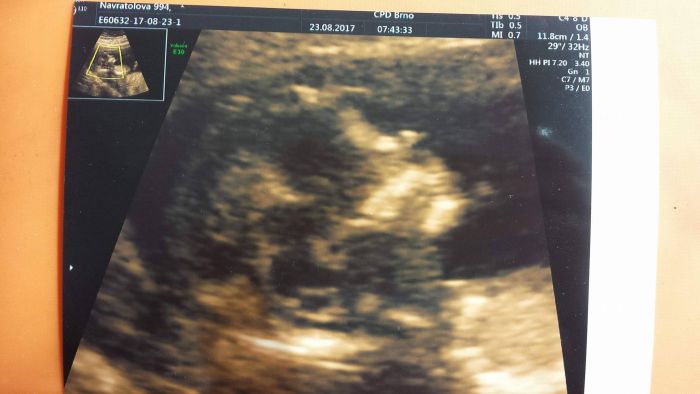

Všechny zdravím, dnes se hlásím s dobrými zprávami :) mám za sebou velký screening a vše dopadlo na jedničku :) jsem 13+3 a mimčo má 73mm. Přikládám fotečku hlavičky. Mějte se hezky a všem přeji dobré výsledky.

[1018329] Moc gratuluju k výborným výsledkům a fotečka je krásná, úžasný detail i projasnění:-)